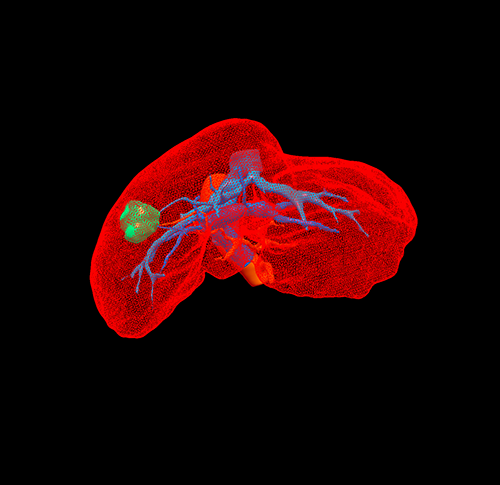

右肝肝癌---右肝肿瘤切除